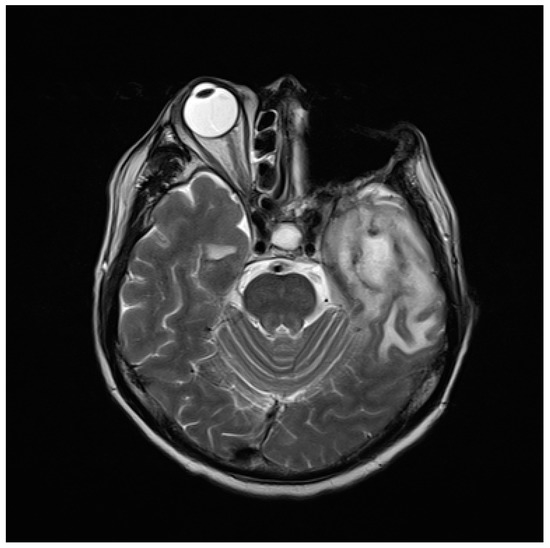

2.1. The Case